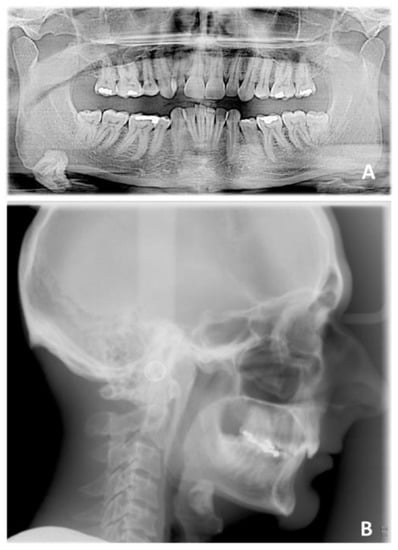

3. Case Report Number 1

The first case reported was an adult male patient who had already undergone orthodontic treatment in the past with the extraction of the four first premolars. The orthodontic situation (Figure 9, Figure 10 and Figure 11 and Table 1) showed a dentoskeletal class II malocclusion, upper and lower crowding, severe deep bite with impingement of the lower incisors on the palate, retroclination of the upper and lower incisors, and convex and biretruded profile. The patient was strongly brachyfacial, and therefore, a deep bite was not only dental but also skeletal. The patient showed good exposure of the upper incisors; therefore, in the resolution of the deep bite, it was preferable not to intrude upper incisors in order not to worsen the patient’s aesthetics.

The treatment was conducted exclusively with clear aligners and followed the protocol for the resolution of the deep bite that was described above. It lasted approximately 18 months, with only one little refinement. At the end of the treatment, the resolution of the deep bite and an important leveling of the patient’s curve of Spee was clearly evident, as can be seen in the comparison between the initial and final orthopantomography.

The exposure of the lower incisors at the end of the treatment was normal, the upper and lower crowding was resolved, and the dental class was corrected. In fact, at the end of the treatment, the patient was in molar and canine class I. Cephalometric analysis (Table 2) showed skeletal deep bite, skeletal class II, and better inclination of upper and lower incisors. At the end of the treatment, intra- and extra-oral photos of the patient and X-rays were taken (Figure 12 and Figure 13) and, after few days, a removable Essix for long-term retention was delivered. Final cephalometric tracing is showed in Figure 14.

Figure 10. Pre-treatment radiographic of case number 1: (A) orthopantomography; (B) lateral cephalogram.